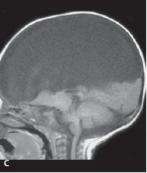

顱裂好發于顱骨的中線部位,顱頂及顱底均可發生。以枕部多見,也見于額頂部;顱底部者可自鼻根部、鼻腔、鼻咽腔或眼眶等部位膨出。個別病例可向側方膨出。隱性顱裂,外表無包塊。囊性顱裂可分為腦膜膨出或腦膜腦膨出,后者囊內含有組織,或部分擴張的腦室等。這種情況下,頭顱常為小頭,而膨大部分特別大。包塊基底或大或小。